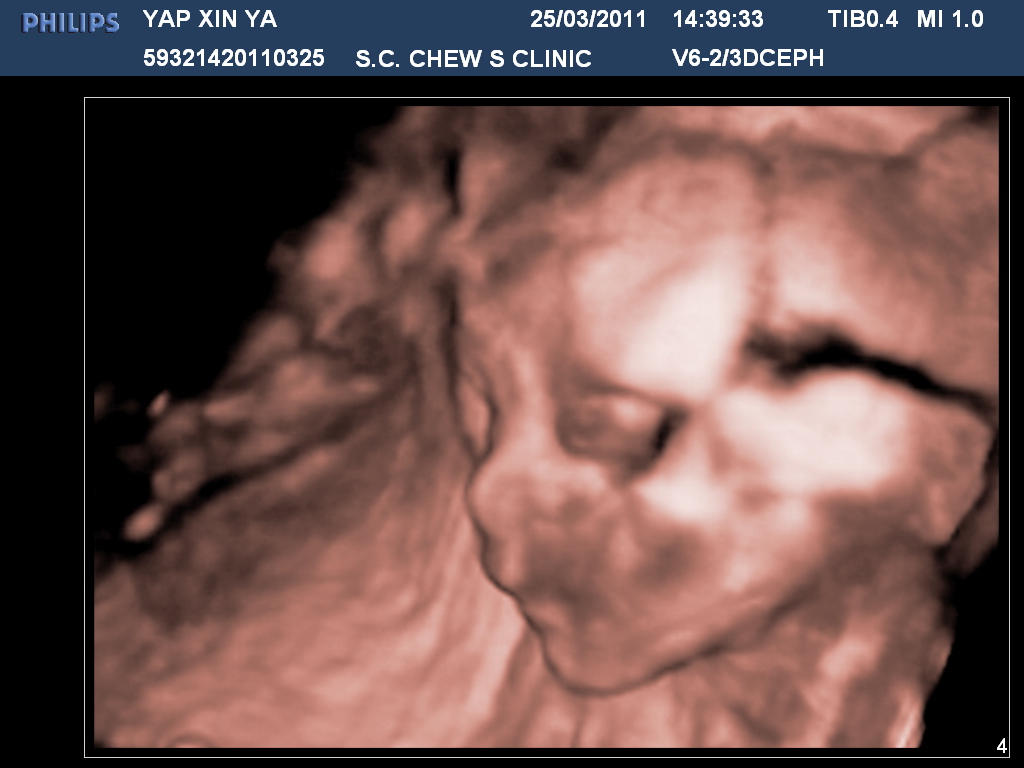

CONFIRMED ITS A GIRL. SO SHE'S MAKAYLA!

okay...next...wad do i have...oh, Her height is 29.1875......A LOT TALLER den normal babies her age. ^^ My baby is 'taller' or 'longer' than 77% of american babies and of course, at least 80% taller den asians...so here's her beautiful pics!

| ISSN"T SHE CUTE?!! |